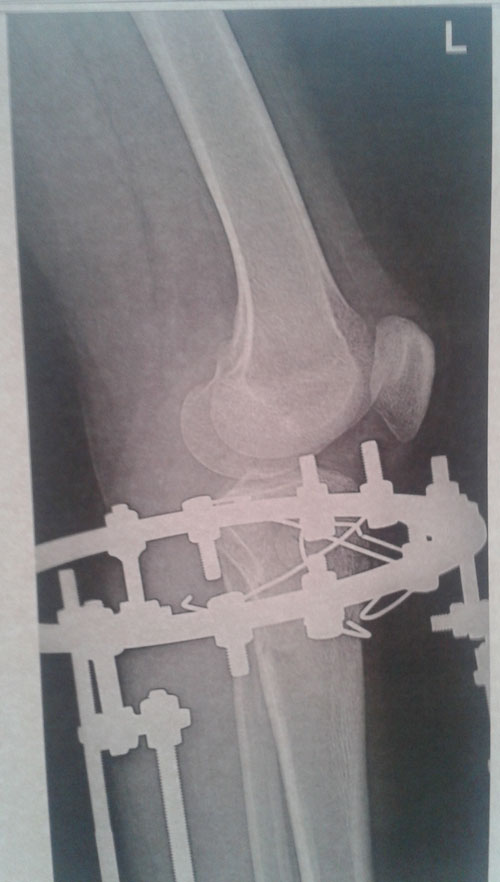

Рентген перед снятием аппаратов.

Сращение отличное!